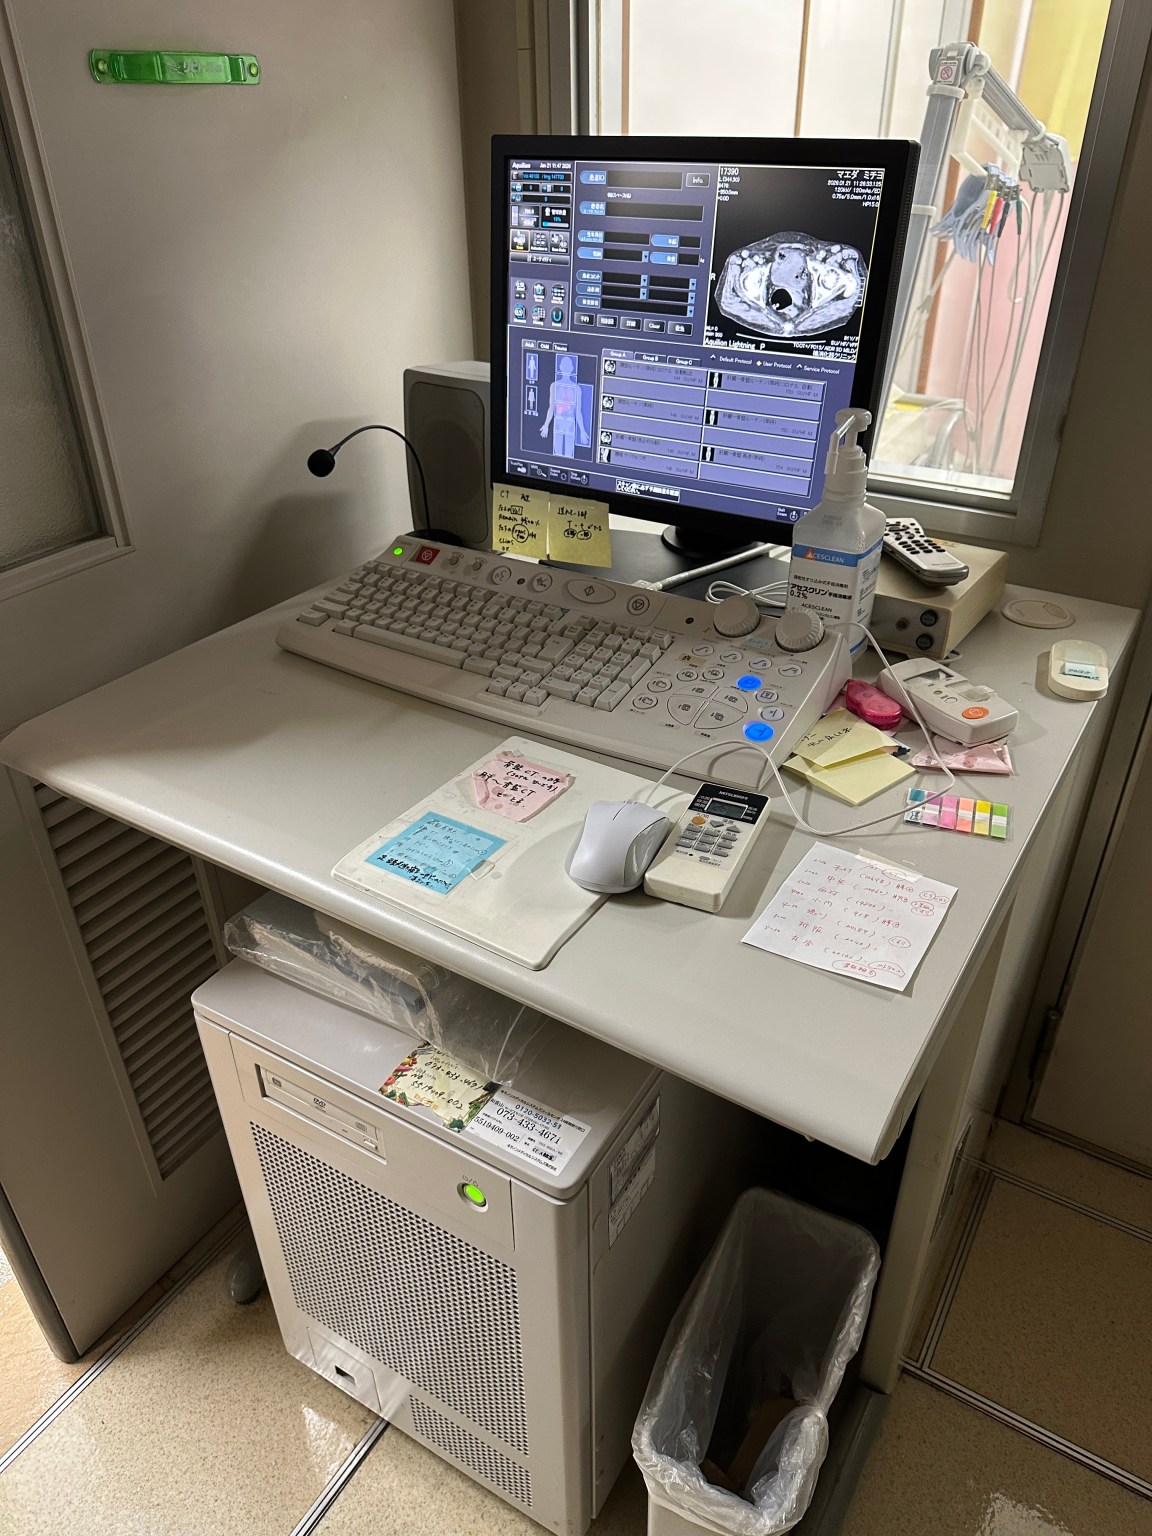

Descripción

| Manufactured | : | November 2018 |

| Location | : | Japan (NEX325) |

| Tube Manufactured | : | June 2025 (Almost new tube) |

| Tube Replaced | : | October 2025 |

| Tube Slice Time | : | 9779 sec |

| Tube Exposure Count | : | 11,157 |

| Installed Options | : | ALATO_3DVIEWER, ALATO_MULTISLICECT, ALATO_STANDARD, DCM_CDR, DIM_EXP, DOUBLESLICE, D_PRT_BW, D_PRT_COLOR, MULTIVIEW, PRINT_SCU, REALEC, REAL_PREP, REAL_VIEW, STRG_SCU, TIFF, TOS_SERVICE, TSB_DVD, WINPRT |